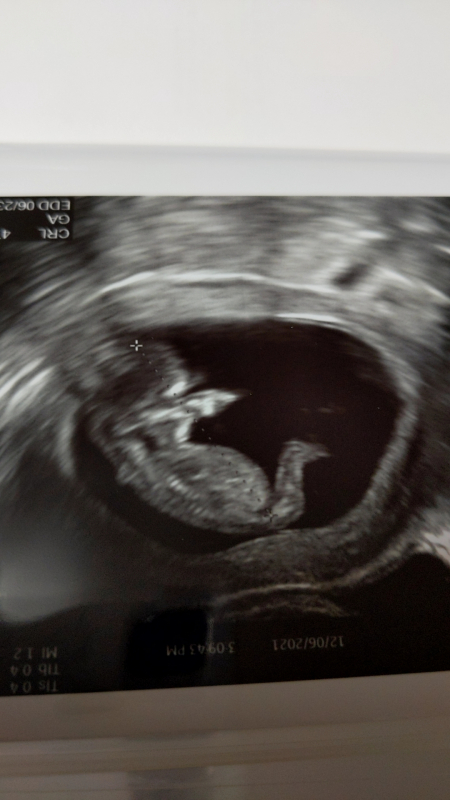

このたび妊娠4ヶ月検診を受けまして、エコーの写真を見たところ、足の向きが逆になっているように感じました。

写真も載せさせていただきます。

これは赤ちゃんの位置の関係でしょうか?それともなにか考えられることがあるのでしょうか?

エコーの赤ちゃんの足の向きについてですね。

動いている瞬間を捉えているものになりますので、動かした瞬間の静止画像になっていて、足の向きに違和感を感じるのかな?とも思いました。